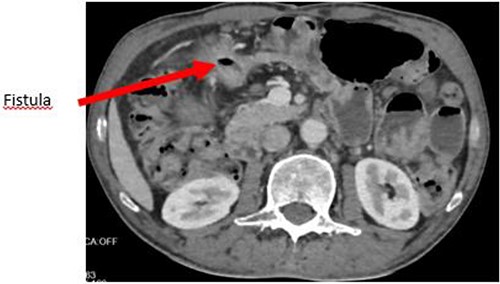

The enteroscan showed a large fistula between the anterior face of the stomach, the jejunum and the transverse colon (Figs 2 and 3). The diagnosis of GJF was then established. The patient underwent surgery. A revision gastrectomy, truncal vagotomy and segmental resection of the jejunum and transverse colon with Roux-en-Y reconstruction were performed. During the follow-up, the patient remained well and gained weight.

Axial section showing the large GJF with stranding of the surrounding fat.